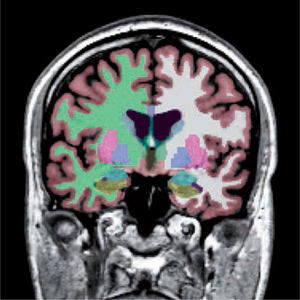

Las alteraciones de la estructura se pueden estudiar más detalladamente utilizando imágenes de resonancia magnética que cubren cada milímetro del cerebro (volumétricas) (Figura 1), desde las cuales es posible separar artificialmente mediante software, las distintas estructuras del cerebro (segmentación) (Figura 2) y poder comparar el tamaño de estas estructuras con una población de sujetos normales de la misma edad. Actualmente es posible obtener volúmenes de cada una de las estructuras como hipocampos, ganglios basales, cerebelo, etc. de nuestro paciente (Figura 3). Además, utilizando esta misma información es posible realizar imágenes tridimensionales del espesor de la corteza cerebral en cada hemisferio (Figura 4).

Segmentación de las distintas estructuras cerebrales de un sujeto normal. Corteza (rojizo), sustancia blanca (derecha: verde, izquierda: blanca), ganglios basales, hipocampos (verde) y amígdalas (celeste).

Software Freesurfer (http://ftp.nmr.mgh.harvard.edu/).